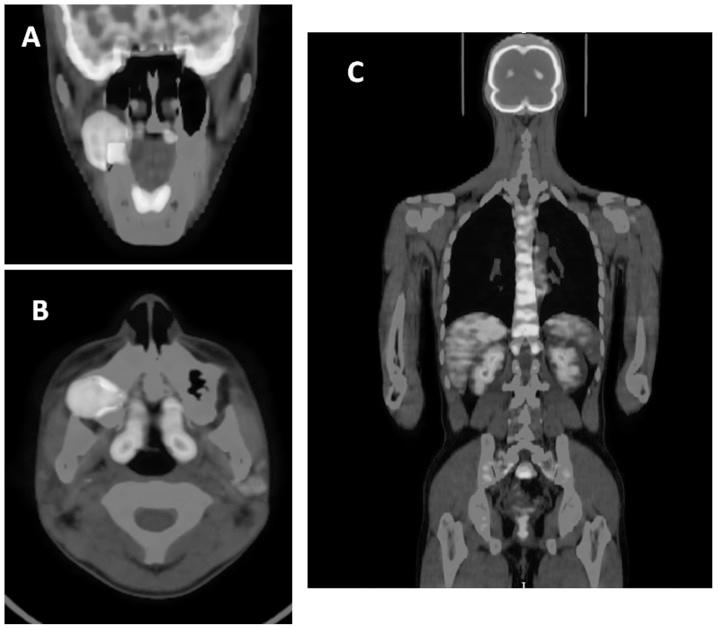

Ameloblastic carcinoma (AC) is a rare malignant odontogenic neoplasm that tends to occur in the mandible rather than in the maxilla. This malignancy is classified as a tumor that combines the morphological features of ameloblastoma and carcinoma, regardless of the presence or absence of metastasis. In addition, AC has been classified into two types, primary and secondary. The former develops and the latter develops by malignant transformation of a pre-existing benign ameloblastoma. The present study describes the case of a 22-year-old patient with primary AC of the maxilla. A review of the literature focusing on the clinical details, treatment results and histopathological and phenotypic information available for ameloblastic carcinoma of the maxilla from a 60-year period was also performed. As a result, it was found that primary AC is dominant in the maxilla and does not exhibit an aggressive phenotype compared with secondary AC. In addition, the presence of recurrence was found to correlate with mortality, indicating that early, aggressive and complete removal of the tumor is the best treatment for survival.

成釉细胞癌(AC)是一种罕见的恶性牙源性肿瘤,多发生于下颌骨而非上颌骨。这种恶性肿瘤被归类为一种兼具成釉细胞瘤和癌形态学特征的肿瘤,无论有无转移。此外,AC可分为原发性和继发性两种类型。前者为原发性发生,后者由先前存在的良性成釉细胞瘤恶变而来。本研究描述了一名22岁上颌骨原发性AC患者的病例。还对60年间上颌骨成釉细胞癌的临床细节、治疗结果以及组织病理学和表型信息进行了文献综述。结果发现,原发性AC在上颌骨中占主导地位,与继发性AC相比,不表现出侵袭性表型。此外,发现复发的存在与死亡率相关,这表明早期、积极和彻底切除肿瘤是生存的最佳治疗方法。